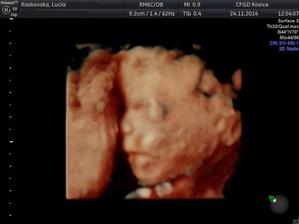

♥ 16.september prvotrimestrálny skriníng v 12tt (v Myslave) všetko v poriadku, odber krvi a máme prvé 3D fotky a na 80% potvrdené pohlavie 🙂

♥ 12.november druhotrimestrálny skriníng v 20tt+1 (v Myslave), všetko je v poriadku, náš chlapček váži 292g,ale 3D fotky nemáme, lebo náš chlapček trucoval obrátil sa chrbátikom a nechcel sa otočiť z profilu 🙂 takže o 2 týždne ideme znovu tak uvidíme či sa náš chlapček ukáže tak ako by mal 🙂

@barbora1992 a na druhotrimestralnom skriningu som bola preto 2krat lebo náš chlapček trucoval a nechcel sa otočiť z profilu tak nás objednali na druhýkrát aj to znovu náš chlapček trucoval a až po 3hod. prechádzke keď som išla dnu sa konečne aspoň trochu otočil tak ako mal, lekár si chcel pozrieť tvár aj z profilu aby sa uistil, že je všetko v poriadku 🙂